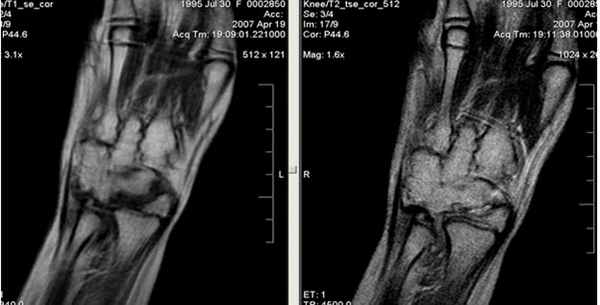

МРТ кисти. Корональная Т1-взвешенная МРТ. Нормальное изображение ладьевидно-полулунной связки. Обозначения: S – ладьевидная кость (scaphoid), L – полулунная кость (lunatum), T- трехгранная кость (triquetrum).

МРТ кисти. Корональная градиентная МРТ. Нормальное изображение полулунно-трехгранной связки. Обозначения: S – ладьевидная кость (scaphoid), L – полулунная кость (lunatum), T- трехгранная кость (triquetrum).

(Слева) МР-артрография в режиме Т1ВИ FS, коронарный срез: определяется разрыв тыльной части ЛПС. Контрастный препарат через дефект распространяется в среднезапястный сустав. Также отмечается разрыв треугольного фиброзно-хрящевого комплекса (ТФХК), вследствие ко торого контрастный препарат поступает в дистальный лучелоктевой сустав.

(Справа) МР-артрография в режиме Т1ВИ FS, коронарный срез, этот же пациент: определяются разрывы мембранозной части ЛПС и мембранозной части треугольного фиброзно-хрящевого диска. (Слева) МР-артрография в режиме Т1ВИ FS, аксиальный срез: визуализируется интактный тыльный пучок, ладонный пучок поврежден. Следует отметить расширение суставной щели, истончение хряща и кисто-зоподобную перестройку.

(Справа) МР-артрография в режиме Т1ВИ FS, коронарный срез: определяется консолидированный перелом дистального отдела лучевой кости. Конгруэнтность суставных поверхностей нарушена. В ладьевидно-полулунном промежутке видна рубцовая ткань. Отмечается распространение контраста в среднезапястный сустав, что, вероятно, обусловлено рубцеванием или сбросом контрастного препарата из лучезапястного сустава в дистальный лучелоктевой сустав через дефекте ТФХК. (Слева) Артрография, заднепередняя проекция, кисть отклонена в локтевую сторону: визуализируется увеличение ладьевидно-полулунного промежутка, однако контрастный препарат в среднезапястный сустав не поступает.

(Справа) МР-артрография в режиме Т1ВИ FS, коронарный срез, этот же пациент: отмечается, что ладьевидно-полулунная связка интактна. Выявленные изменения свидетельствуют о ее заживлении после разрыва.